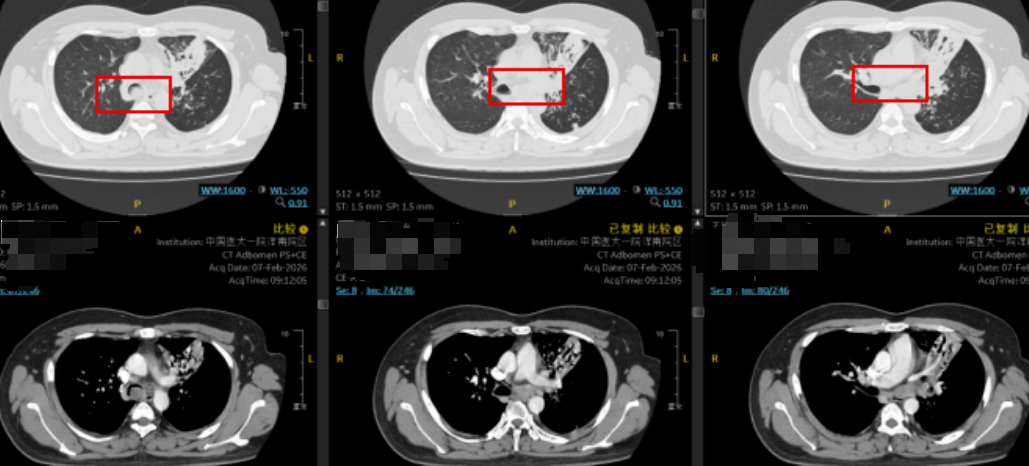

在呼吸科医生赶到前,急诊科接诊医生已为患者紧急完善了初步的化验检查并及时给予对症处理,刘亭威查看CT检查结果,提示患者主气管及左主支气管内可见条状实性病变,管腔严重狭窄,左肺周围见炎性病变。这些改变正是导致患者急性呼吸困难的原因。

CT可见肿物阻塞左主支气管(红框所示),并延伸至隆头上主气管处,阻塞部分右主支气管开口